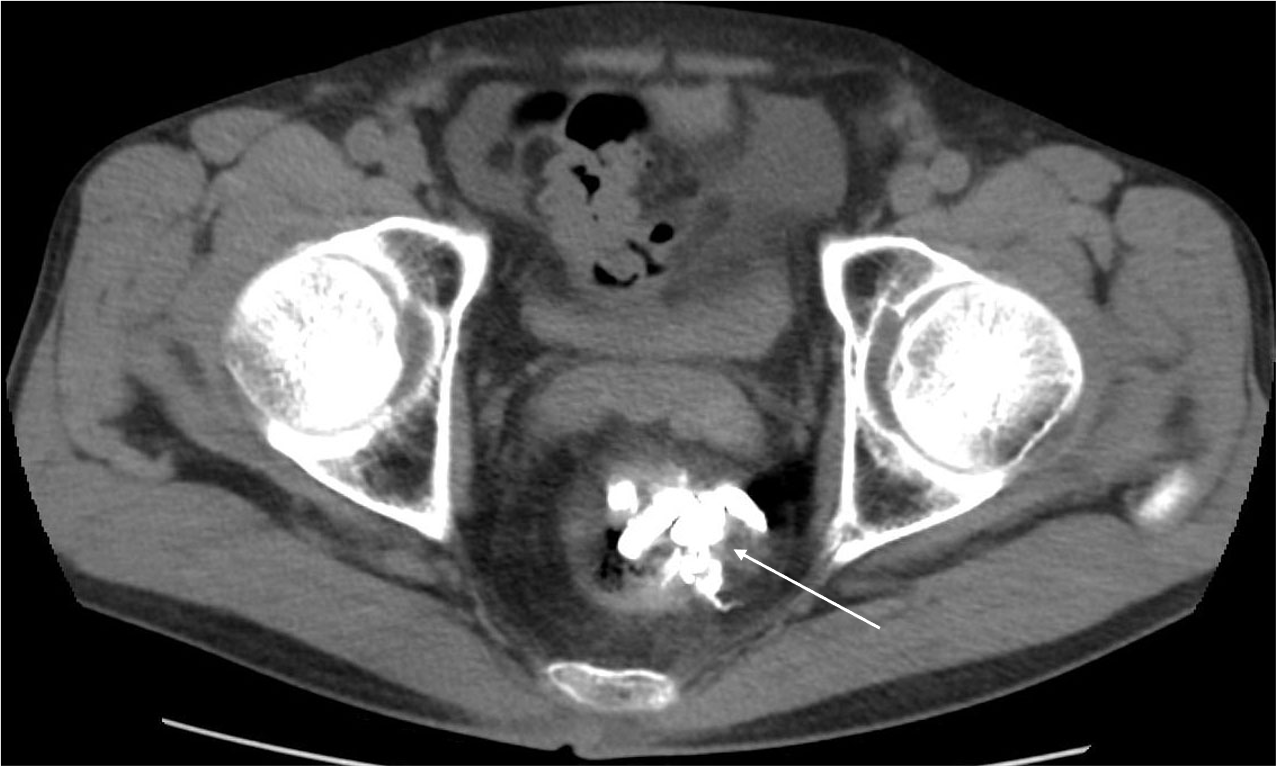

直腸静脈瘤の破裂予防目的にヒストアクリルを用いた経皮経肝的静脈瘤塞栓術を施行した。治療一か月後の治療効果判定に撮影を行った。

肝硬変のスクリーニング目的の造影CTにて直腸静脈瘤が判明した。破裂予防目的に経皮経肝的静脈瘤塞栓術を施行した。術前CTにて血管解剖を把握の上、治療を行った。術後一か月の造影CTにて、標的血管の良好な閉塞が確認された。

当該疾患の診断における造影CTの役割

直腸静脈瘤を始めとする異所性静脈瘤においては、IVR治療が選択されることが多い。術前に正確な解剖の把握が必要であり、造影CTの果たす役割は大きい。特に門脈系の良好な描出が求められ、適切な時相での撮影が肝要である。撮影後thin slice軸位断像での観察、任意多断面再構成像(MPR)やVolume rendering画像(VR)で評価を行い、術中のガイドとする。また肝細胞癌を併発することが多い為、動脈優位相における撮影も行う必要があり、dynamic studyを要する。治療においてはヒストアクリルや金属コイルなどのアーチファクト源となり得るデバイスが使用されるため、必要に応じてmetal artifact除去を活用する必要がある。また別部位に新たな静脈瘤が生じたり、腹水などの門脈圧上昇に伴う所見や門脈血栓などの合併症が生じる危険性があるため、造影CTによる評価が重要である。

CT技術や撮像プロトコル設定について

本症例においては、腎機能障害や心不全など、特段併発症を有さない患者様であったため、標準的な撮影プロトコルで撮影を施行した。管電圧は120kVを使用し、逐次近似併用(ASiRV 20%)で再構成を行った。また造影については、536mgI/kgの投与とし、固定法(動脈相 35秒、門脈相80秒後、平行相180秒後)で撮影を行った。ただし肝硬変患者においては、腎機能障害を有することがしばしばあり、その場合には造影剤減量が必要となる。従って低管電圧撮影や逐次近似再構成法、dual energy CTを使ったvirtual monochromatic imageなどを適宜活用する必要がある。また金属コイルなどによる血流改変を施行した場合には、metal artifact除去などを併用して評価を行う必要がある。加えて肝肺症候群などに起因する心機能障害を有することがあり、その場合には固定法による撮影ではなく、bolus tracking法などを活用した撮影が必要となる。